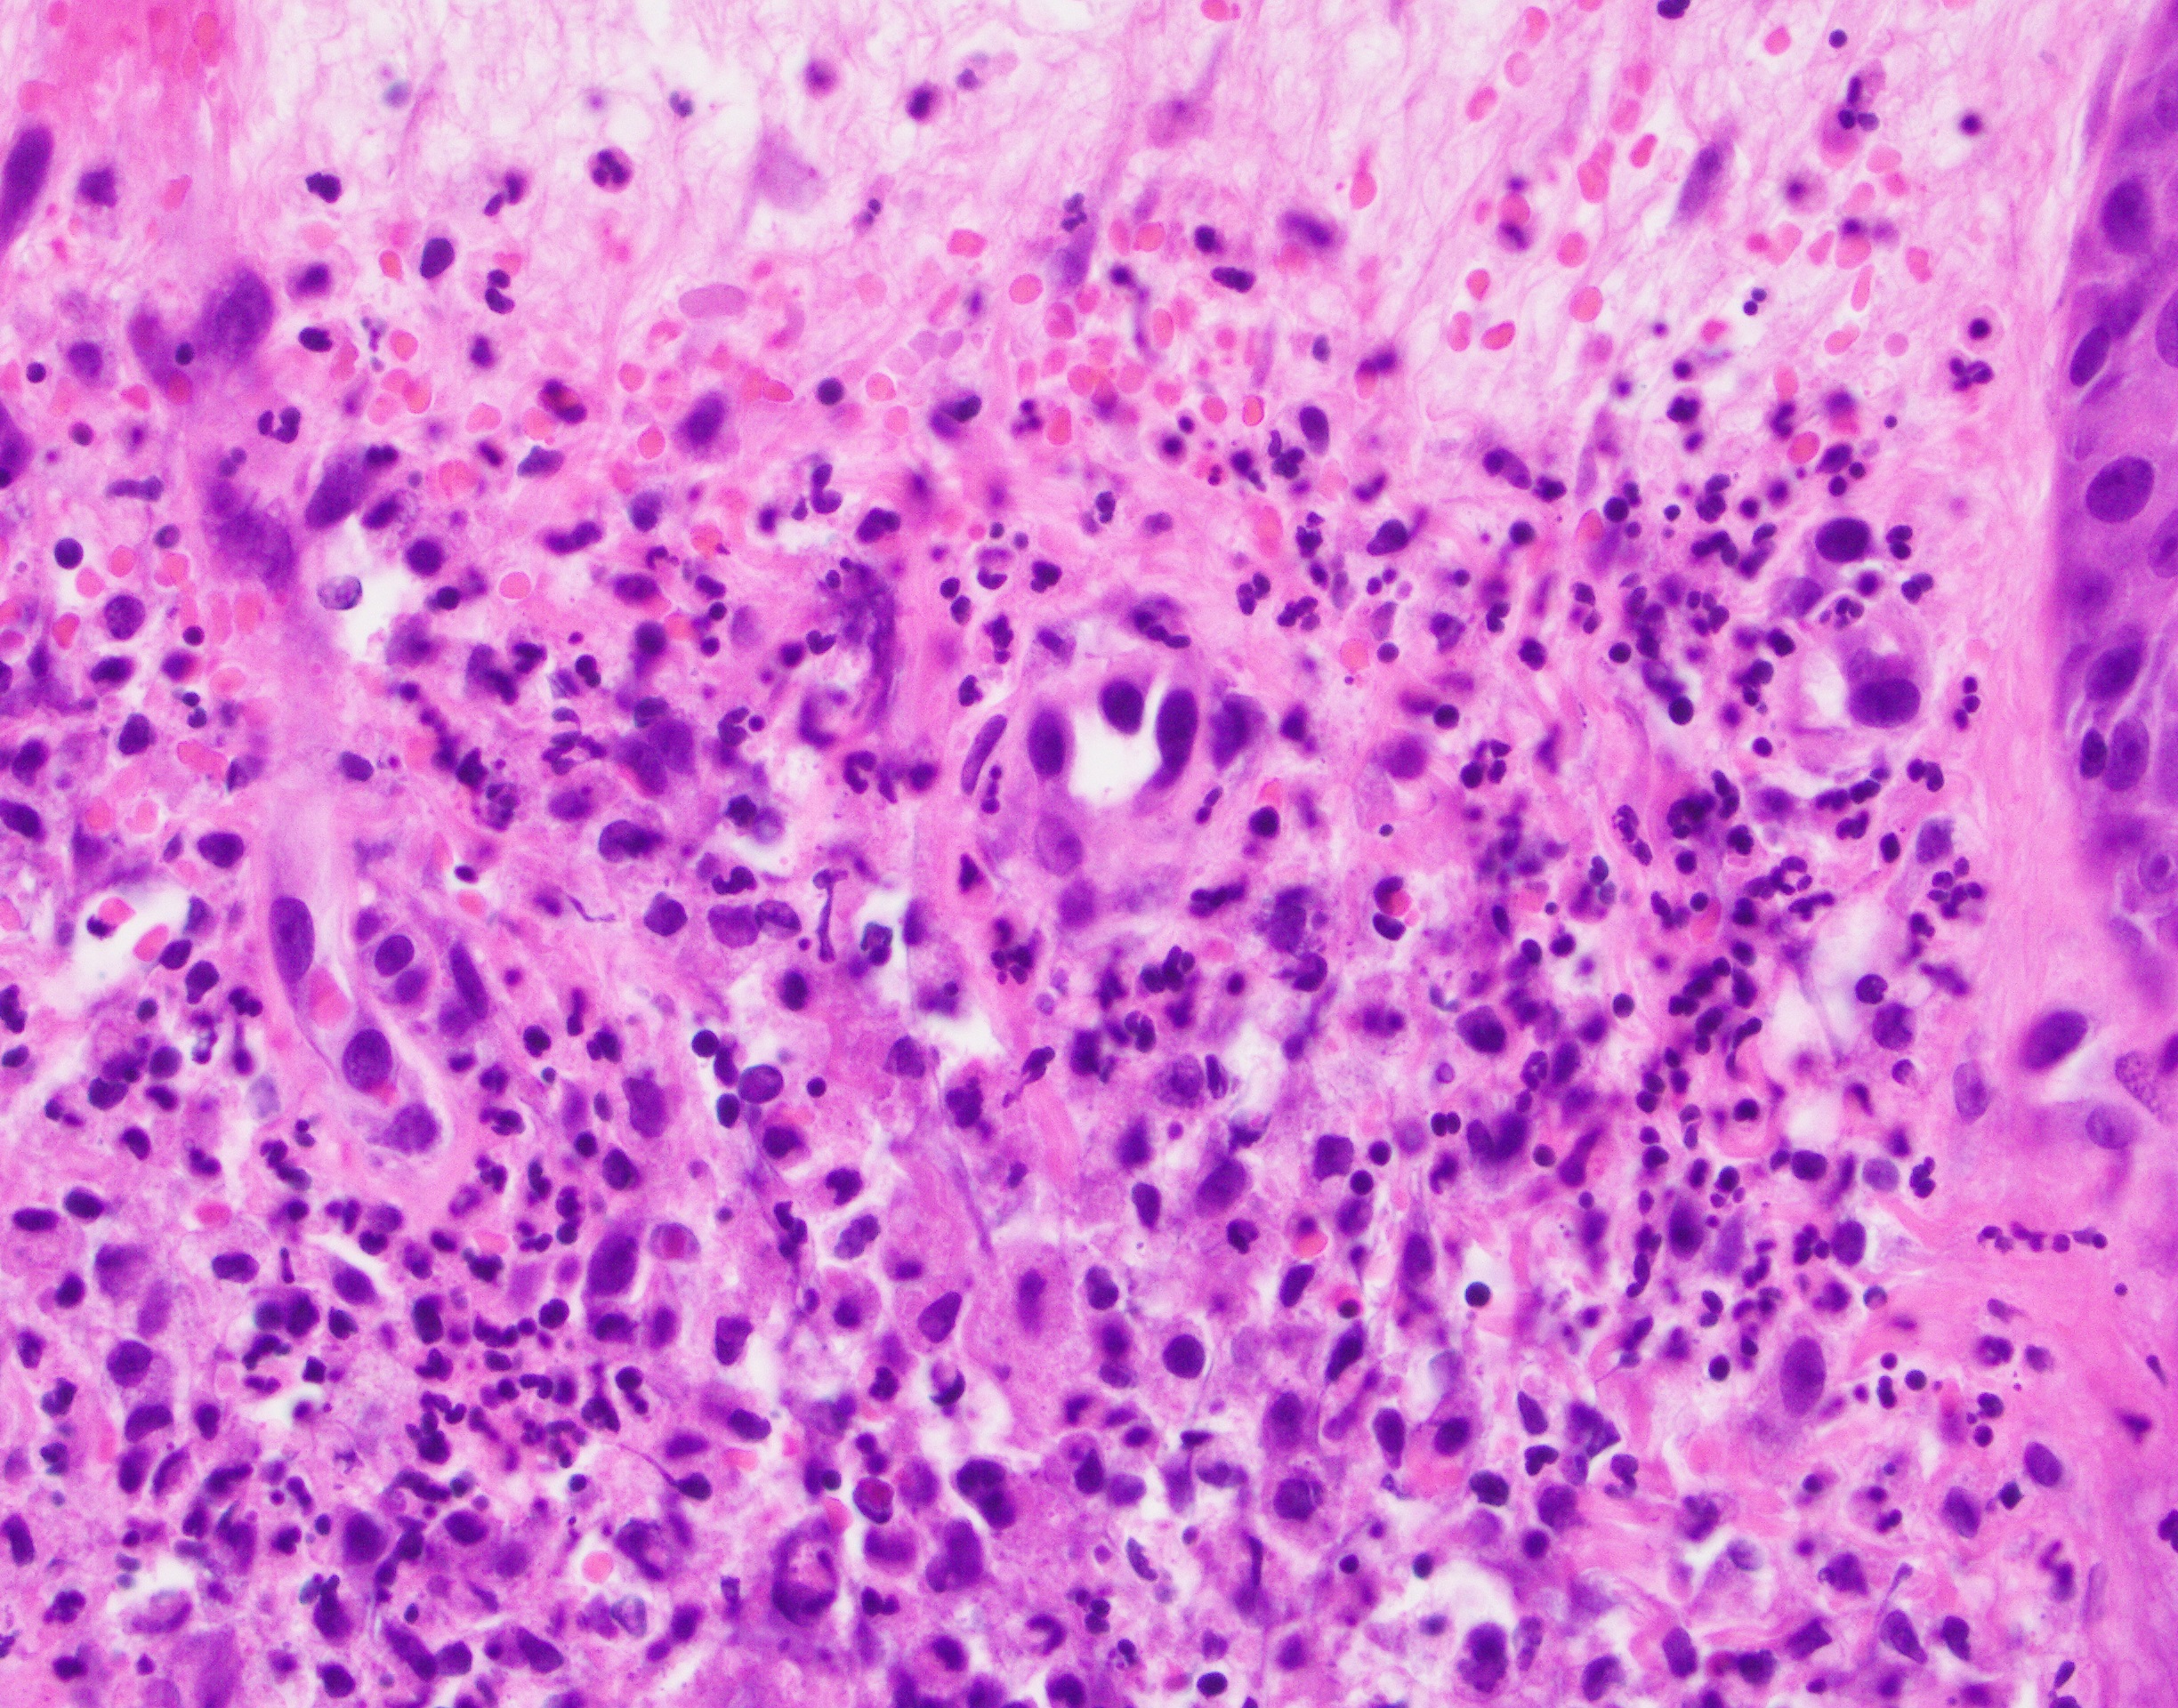

Микропрепараты: Лимфогранулематоз и Нодулярный Склероз